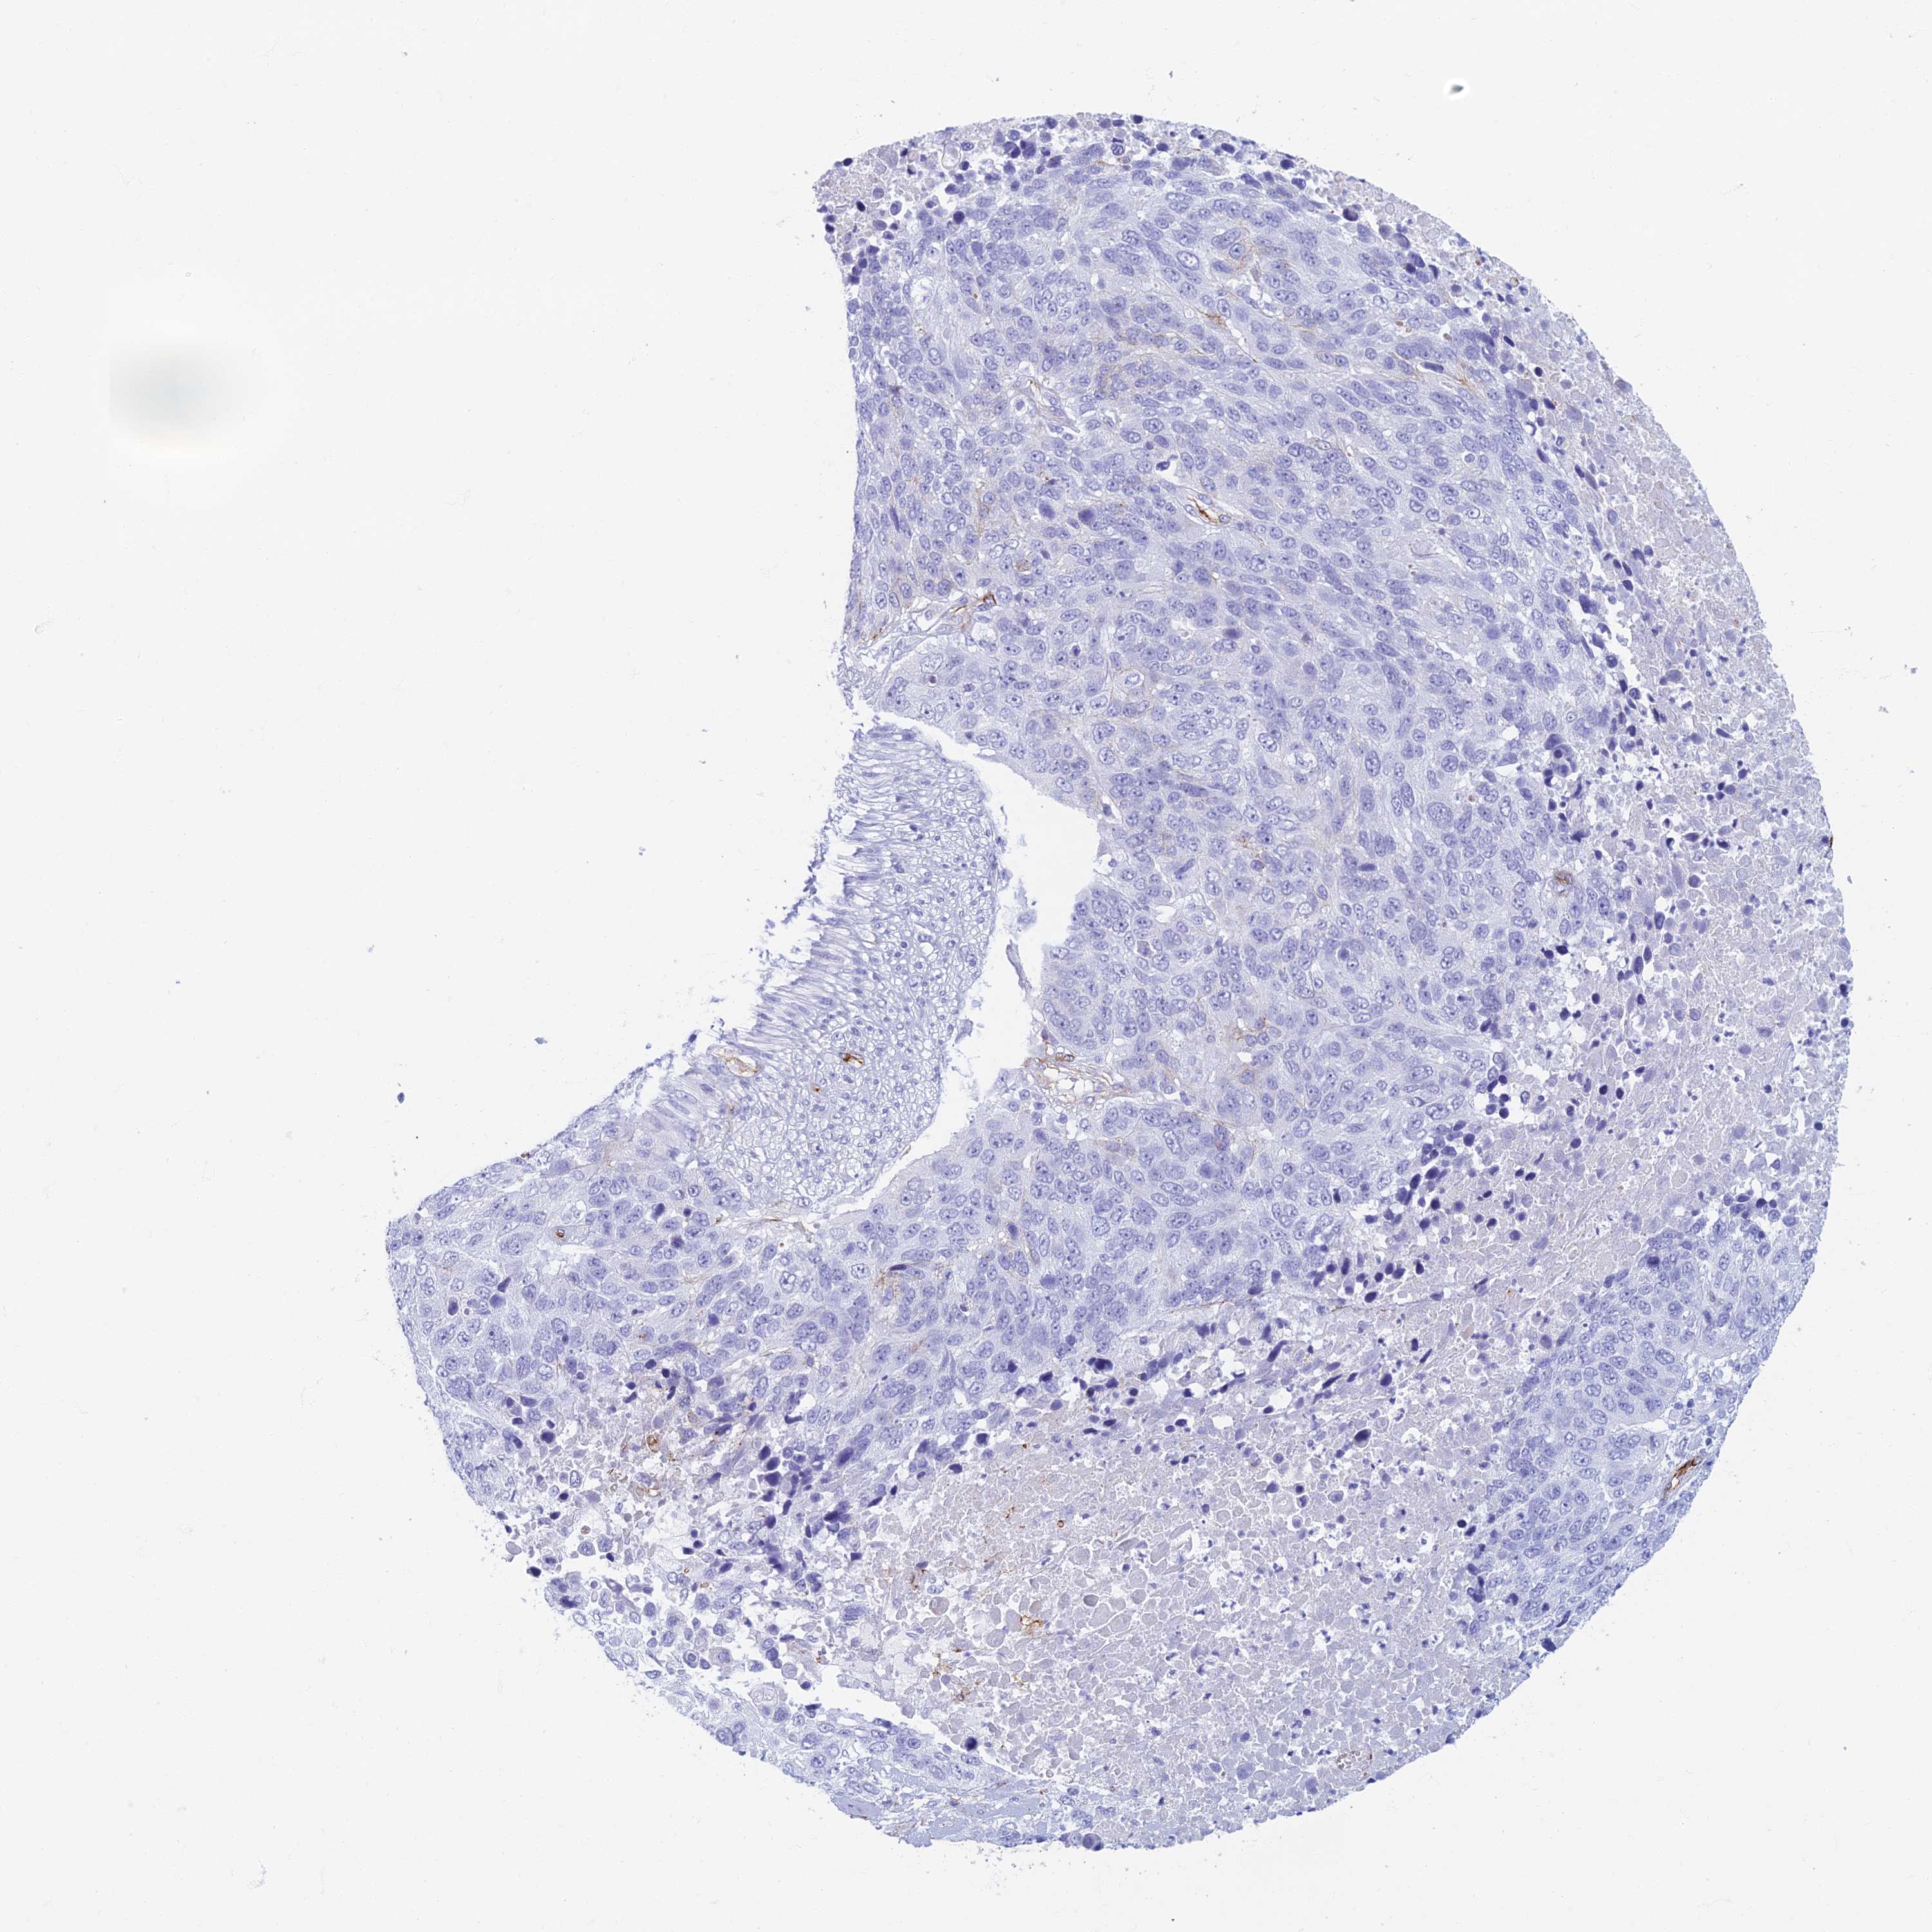

LUNG SQUAMOUS CELL CARCINOMA (TCGA) - Interactive survival scatter ploti

The Survival Scatter plot shows the clinical status (i.e. dead or alive) for all individuals in the patient cohort, based on the same data that underlies the corresponding Kaplan-Meier plots. Patients that are alive at last time for follow-up are shown in blue and patients who have died during the study are shown in red.

The x-axis shows the expression levels (FPKM) of the investigated gene in the tumor tissue at the time of diagnosis. The y-axis shows the follow-up time after diagnosis (years). Both axes are complimented with kernel density curves demonstrating the data density over the axes. The top density plot shows the expression levels (FPKM) distribution among dead (red) and alive patients (blue). The right density plot shows the data density of the survived years of dead patients with high and low expression levels respectively, stratified using the cutoff indicated by the vertical dashed line through the Survival Scatter plot. This cutoff is automatically defined based on the FPKM cutoff that minimizes the p-score. The cutoff can be changed by dragging the vertical line or by entering a cutoff value in the square labeled "Current cut-off".

Under the Survival Scatter plot the p-score landscape (black curve; left axis) is shown together with dead median separation (red curve; right axis). Dead median separation is the difference in median mRNA expression between patients who have died with high and low expression, respectively. It is calculated as follows: median FPKM expression of dead patients with high expression - median FPKM expression of dead patients with low expression. This is intended to aid the user in visually exploring custom cutoffs and the associated p-scores and dead median separation.

Individual patient data is displayed and can be filtered by clicking on one or more of the category buttons on the top of the page. Categories describing expression level and patient information include: high, low, alive, dead, female, male and tumor stages. The scale of the x-axis can be toggled between linear and log-scale by clicking on the "x log" button. Mouse-over function shows TCGA ID, patient information and mRNA expression (FPKM) for each patient.

& Survival analysisi

Kaplan-Meier plots summarize results from analysis of correlation between mRNA expression level and patient survival. Patients were divided based on level of expression into one of the two groups "low" (under cut off) or "high" (over cut off). X-axis shows time for survival (years) and y-axis shows the probability of survival, where 1.0 corresponds to 100 percent.

ETFRF1 is not prognostic in Lung Squamous Cell Carcinoma (TCGA)

: 11.43

P scorei

N/A

Average pTPM 18.5

Number of samples 489